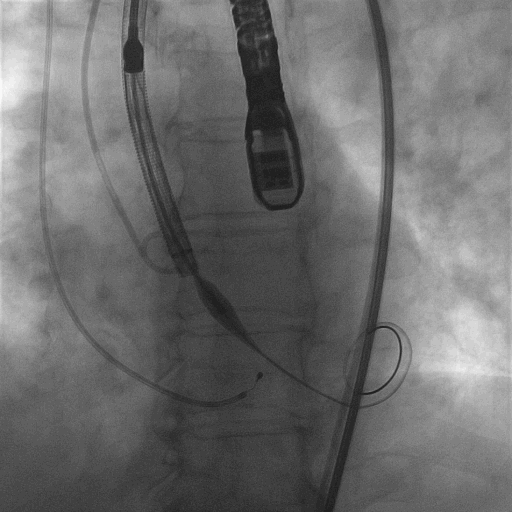

再次释放到2/3,造影观察瓣膜位置良好,选择全部释放

L23高位释放成功

术后结果

跨瓣压差:51mmhg⇢12mmhg

主动脉瓣口峰值流速:5.71m/s⇢2.7m/s